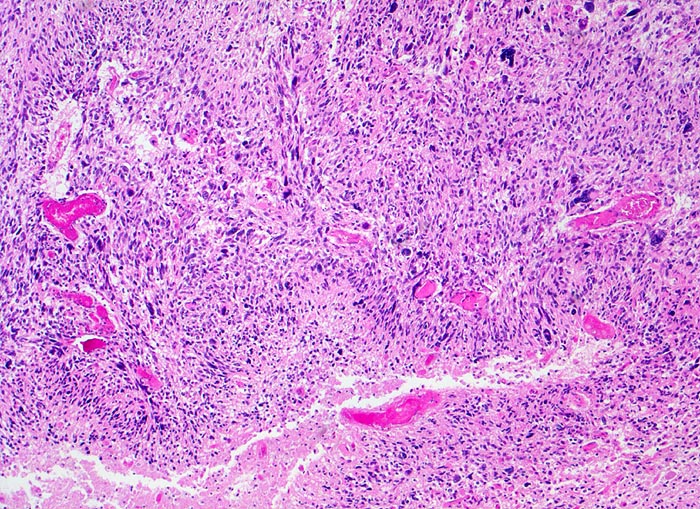

Morphologische Merkmale:

• Zellreicher Tumor mit sehr unscharfer Begrenzung zum normalen Hirnparenchym (rechts unten).

• Typische streifenförmige Nekrosen mit randständiger Palisadierung der Tumorzellen.

• Im Zentrum der Nekrose thrombosierte Gefässe umgeben von einem Saum vitaler Tumorzellen.

• Pathologische glomerulumartige zellreiche Gefässknäuel.

• Ausgeprägte Zellpolymorphie und Atypie.

• Mitosen.